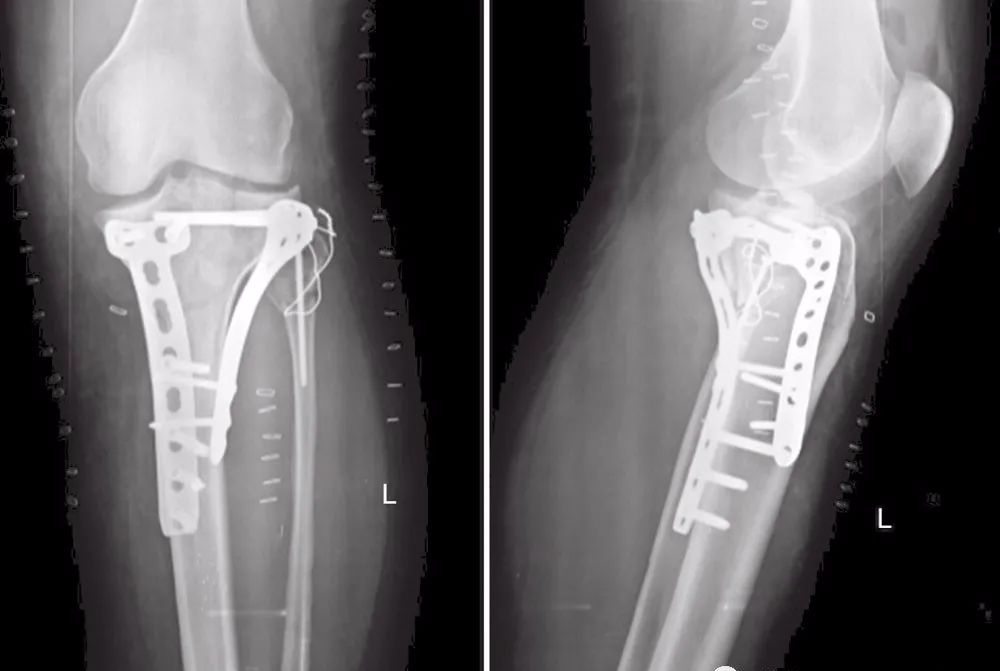

图21 术后X线片

图22 术后1年随访的X线片

27岁男性患者,在交通意外中受伤。他从自行车上跌落,诉左膝严重疼痛,伤后无法站立。这是个单独的损伤。X线片(图17)和CT(图18~图20)显示左胫骨平台双髁骨折。用两块内固定钢板进行开放复位和内固定(图21)。患者术后1年,影像学表现良好(图22),临床功能(图23)恢复良好。